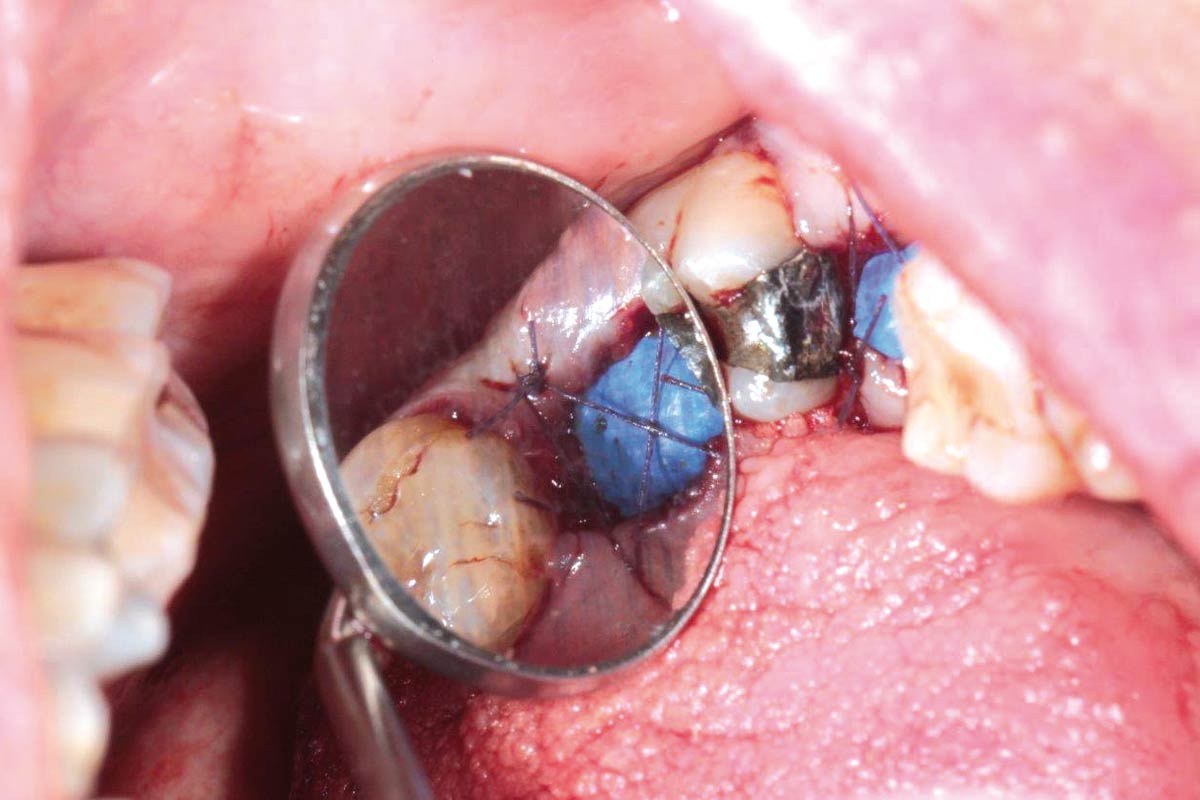

botiss cerabone® & collagen fleece for immediate implantation - Clinical case by Dr. D. Jelušić

Clinical situation before extraction and implantation